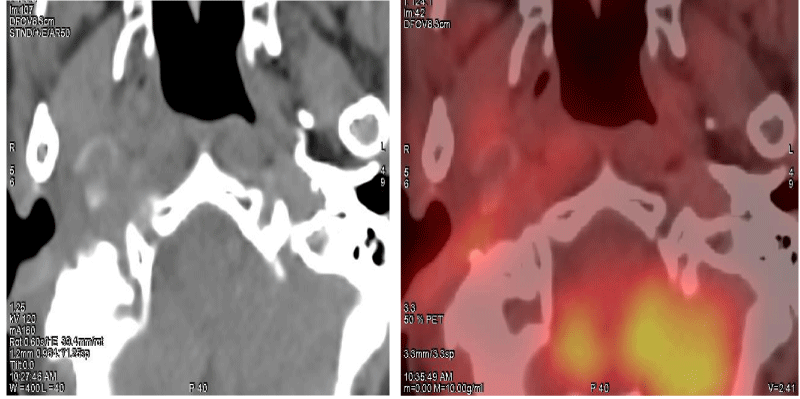

We report a case of 68 years old female with a past history of adenoid cystic carcinoma of right parotid gland post superficial parotidectomy and adjuvant radiotherapy in 2004. Now with complaints of right ear discharge and ear ache since 6 months, on further detailed and systematic evaluation, revealed a mass lesion in the EAC with extension into the infratemporal fossa (Figure 1) which was confirmed to be a well-differentiated Squamous Cell Carcinoma (SCC) on biopsy. After obtaining proper consent and ethical clearance, the patient underwent surgical de-bulking followed by adjuvant EBRT to post-operative residual disease and elective irradiation of ipsilateral nodal levels II and III using the VMAT technique (Figure 2) to a total dose of 66 Gy delivered in 33 fractions, 2 Gy per fraction. The patient tolerated radiotherapy well and was placed under regular follow-up. 12 weeks post EBRT patient was assessed clinically and radiologically with 18F-FDG whole-body PET-CT scan which showed complete morphological and metabolic response (Figure 3). The patient is under surveillance and is doing well.

Download Image

Figure 2: EBRT treatment plan using VMAT technique.